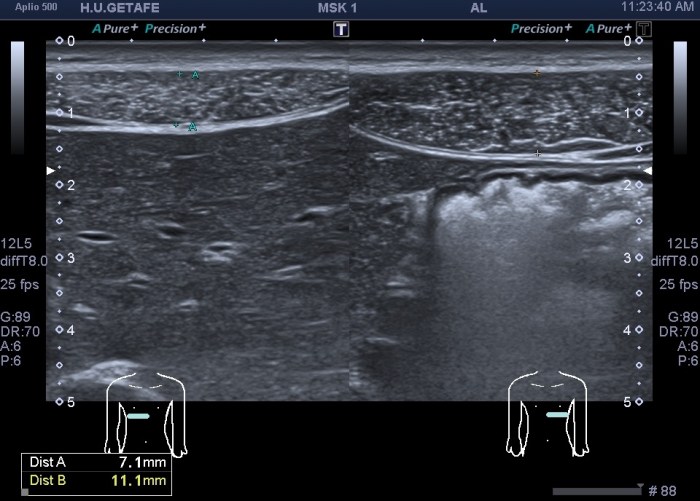

En la imagen 2 podemos ver el primer grupo muscular de los rectos abdominales donde ya observas como el lado derecho es ligeramente más pequeño que su lado izquierdo aunque la ecogenicidad es idéntica.

En la imagen 3, segundo grupo muscular, puedes ver como el lado izquierdo es normal y el derecho está completamente atrófico tanto ecográficamente, como visualmente, como al tacto, por tanto, la sospecha del médico no era más que la normalidad en el lado izquierdo y el aspecto atrófico del lado derecho.

La imagen 6 y 7 es el detalle del segundo grupo muscular de los rectos anteriores para que observes las diferencias entre ambos y puedas valorar ambas semiologías.

En esta ocasión, lo destacable es que la normalidad era lo que a la palpación era sospechoso y que el lado derecho, que parecía normal a la exploración, era el patológico ecográficamente. Llama la atención como todo el grupo muscular derecho está disminuido de tamaño a expensas de una atrofia en el vientre del músculo, que se hace muy evidente en el segundo grupo muscular.